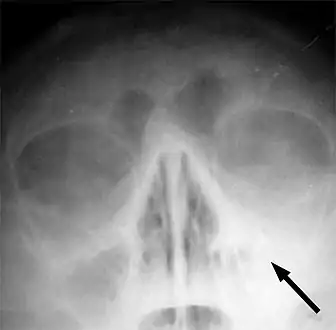

Maxillary sinusitis caused by a dental infection associated with periorbital cellulitis

Frontal sinusitis

X-ray of left-sided maxillary sinusitis marked by an arrow. There is lack of the air transparency indicating fluid in contrast to the other side.